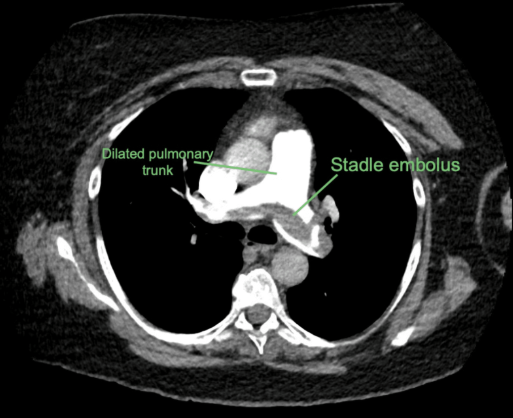

PE: Description

Blood clot in pulmonary arteries

PE: Pathogenesis

DVT in legs/pelvis embolize

IVC → Pulmonary arteries

Obstruct pulmonary arteries

Lung/pleural infarction + inflammation

Impair gas exchange + cardiac function

Pulmonary vasoconstriction

Thromboxane, prostaglandin, adenosine, thrombin, and serotonin secretion from platelets + thrombus

Saddle Thrombus: Clot in pulmonary trunk bifurcation = Complete obstruction = Right heart strain + Death

VTE: CTPA

PE

Obstruction in pulmonary arteries

Pulmonary infarction